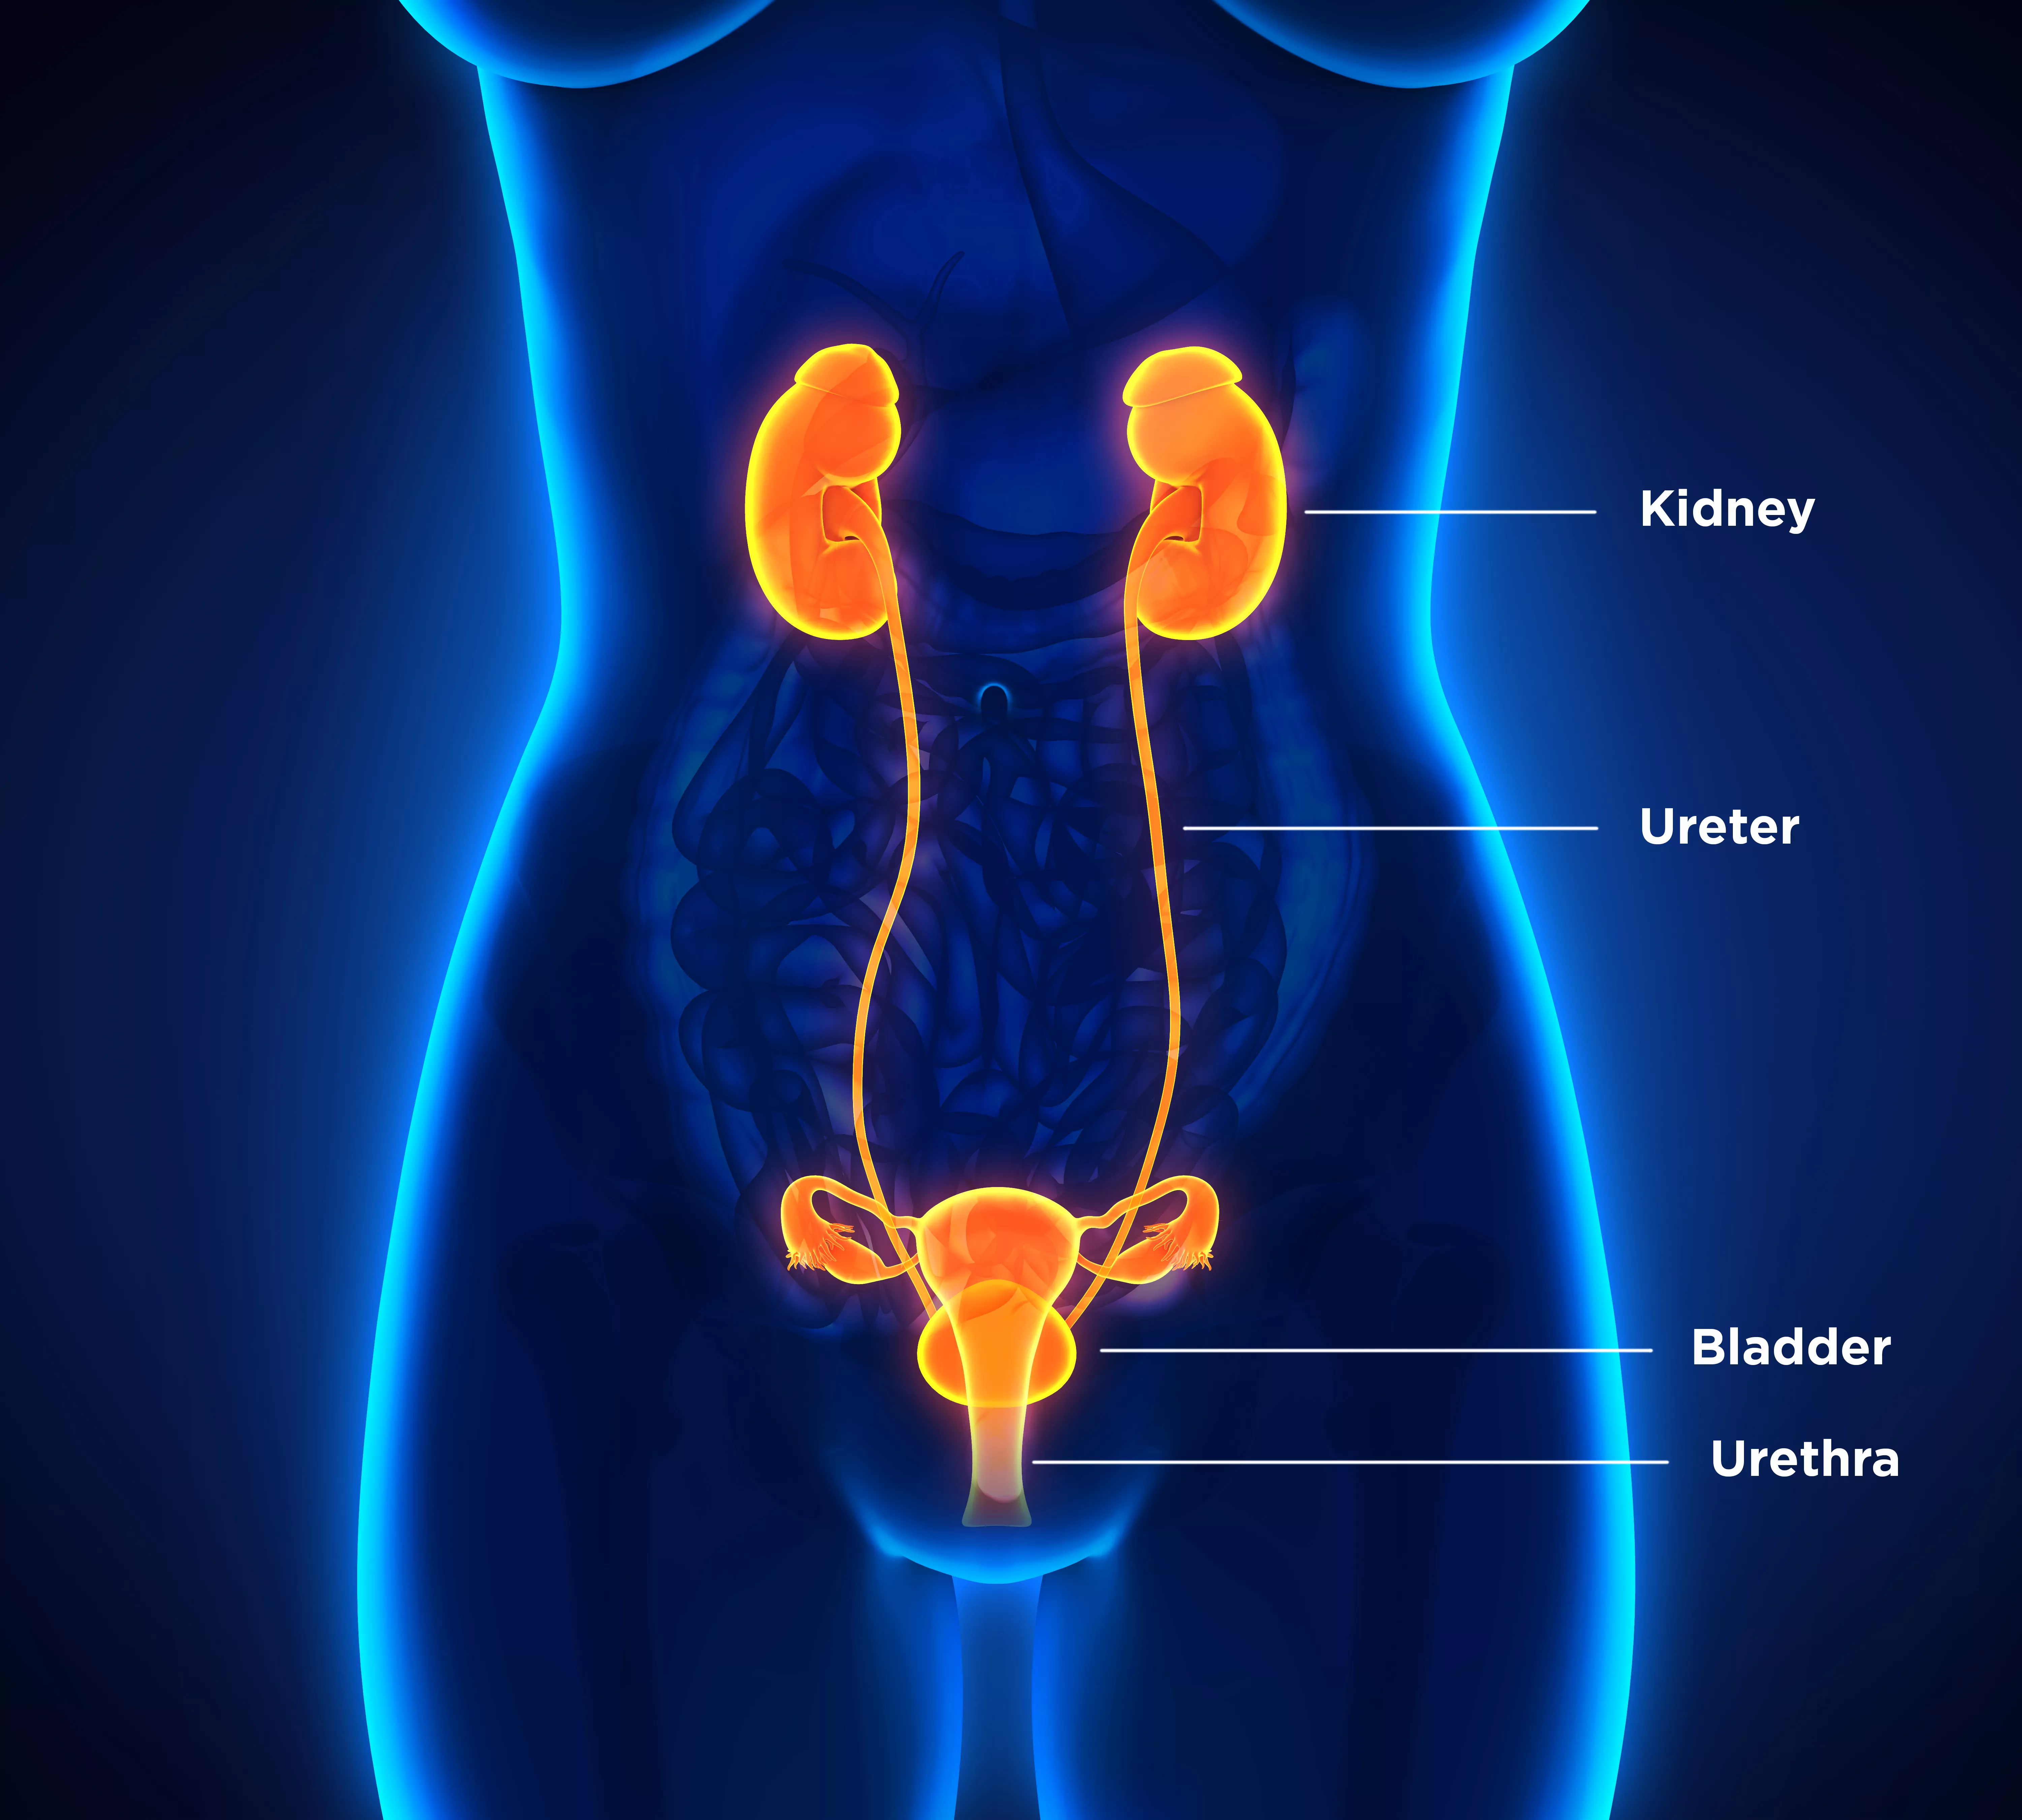

Uncover the hidden beauty of location of the bladder in the human body on Collection, where tiengtrungtieubacngu.edu.vn has gathered a remarkable set of images. The exploration continues in the details.

location of the bladder in the human body

Posts: location of the bladder in the human body